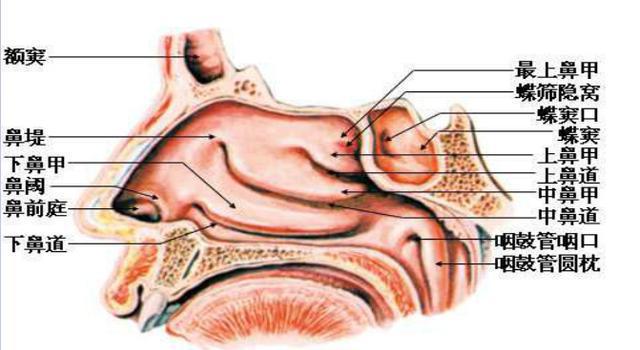

鼻炎----鼻腔粘膜和粘膜下组织的验证表现——充血或水肿,患者经常出现鼻塞,流清水涕,鼻痒,喉部不适,咳嗽等症状

临床表现

变应性鼻炎的典型症状主要是阵发性喷嚏、清水样鼻涕、鼻塞和鼻痒。部分伴有嗅觉减退。

诊断

临床症状喷嚏、清水样涕、鼻塞、鼻痒等症状出现2项以上(含2项),每天症状持续或累计在1小时以上。可伴有眼痒、结膜充血等眼部症状。体征常见鼻黏膜苍白、水肿、鼻腔水样分泌物。变应原皮肤点刺试验阳性,和/或血清特异性IgE阳性,必要时可行鼻激发试验。